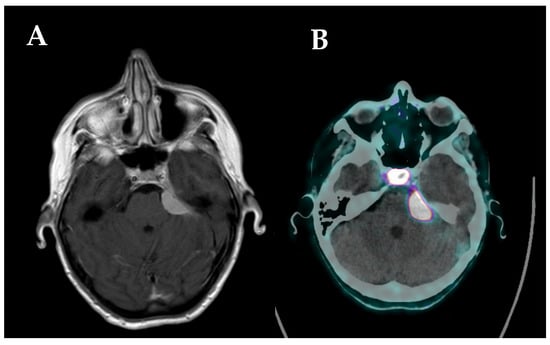

- d’Amico, A.; Stąpór-Fudzińska, M.; Tarnawski, R. CyberKnife Radiosurgery Planning of a Secreting Pituitary Adenoma Performed With 68Ga DOTATATE PET and MRI. Clin. Nucl. Med. 2014, 39, 1043–1044. [Google Scholar] [CrossRef]

| d’Amico, 2014 [36] | Volume contouring for cyber knife | 1/ 1 | Pituitary carcinoma/ DOTATOC | N/A N/A | Improved target definition for pituitary carcinoma invading the cavernous sinus |